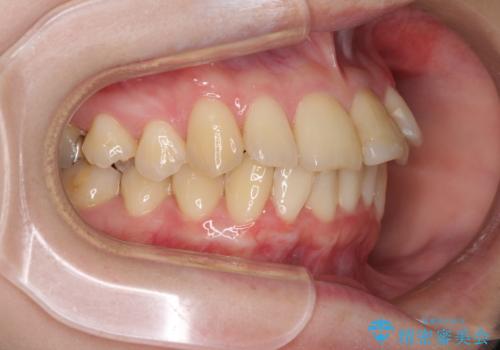

上下前歯のデコボコをきれいに インビザラインによる矯正治療

- 前歯の著しい叢生と前突感を気にして来院された患者様です。

叢生が強いため、事前に前歯をワイヤー矯正で速やかに叢生を解消し、その後はインビザラインにて矯正治療を行うこととしました。

ワイヤー矯正を併用したことで前歯の叢生を速やかに解消することができました。

一方口元の突出感を改善するために時間がかかり、2年超を要しましたが、満足のいく仕上がりとなりました。